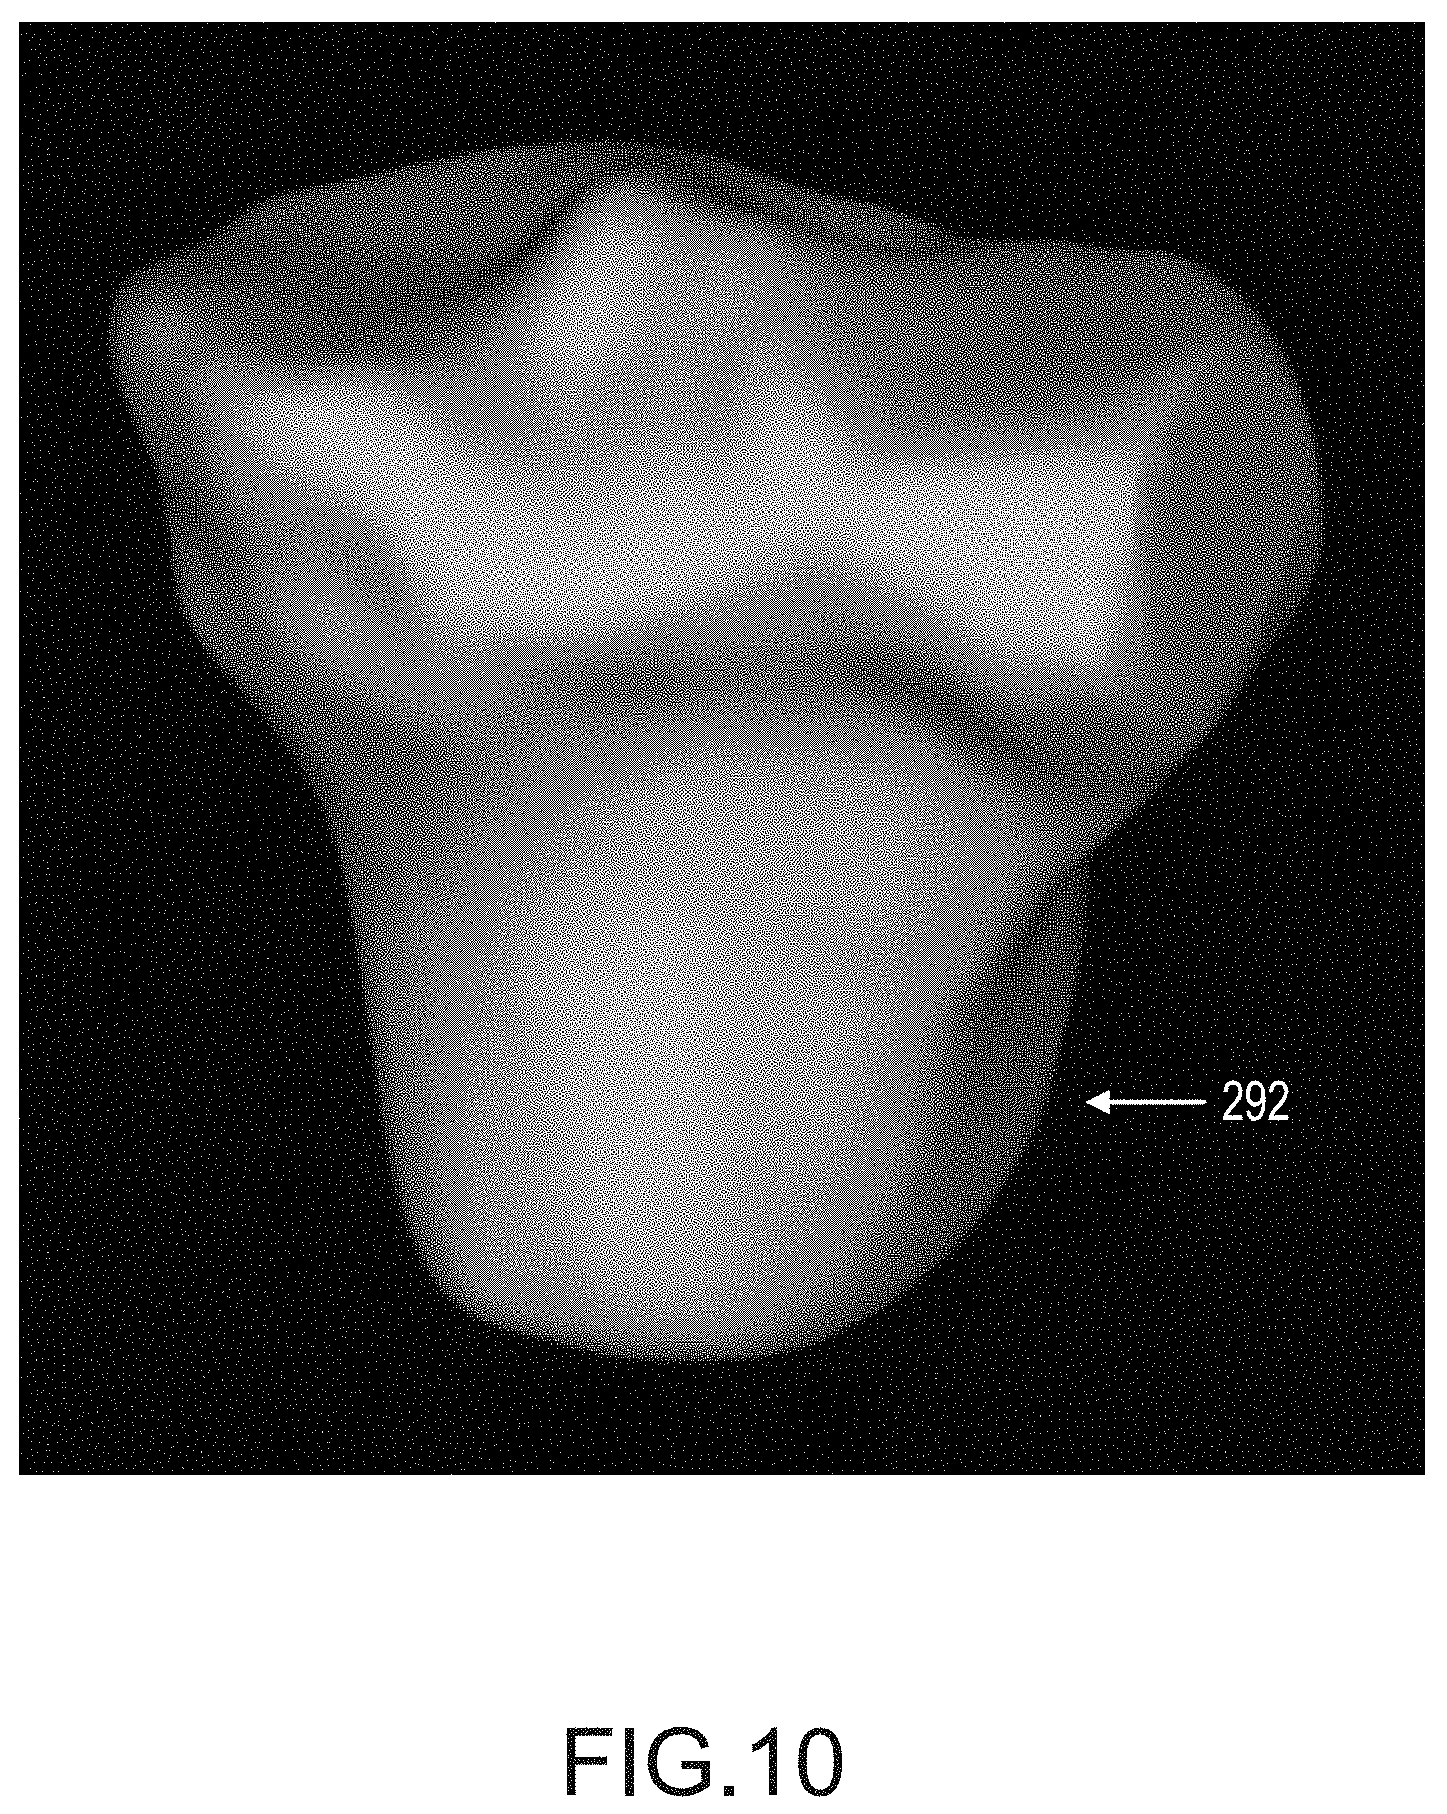

FIG. 10 depicts a 3D mesh geometry of a tibia.

Once the technician is satisfied with all of the tibia spline curves in the scan slices, operation 262 generates a watertight triangular mesh geometry from the tibia segmentation. The mesh closely follows the spline curves and smoothly interpolates between them to generate a 3D surface model of the tibia. FIG. 10 depicts a typical 3D mesh geometry 292 of a target tibia generated by one embodiment. Such a 3D model may be a 3D surface model or 3D volume model resulting from open-loop contour lines or closed loop contour lines, respectively. In one embodiment, such a 3D model as depicted in FIG. 10 may be a bone model 22 or an arthritic model 36.